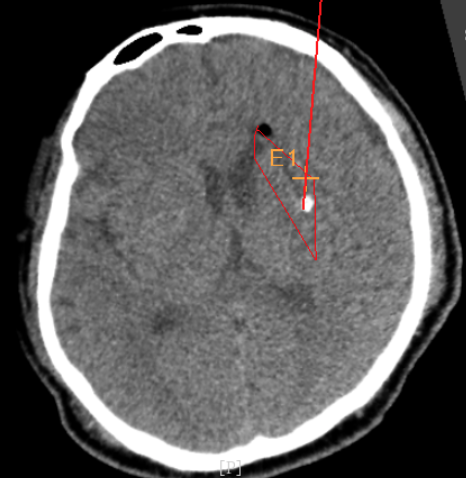

韓帥醫(yī)生借助機(jī)器人操作平臺順利抽出血性液體15ml,與術(shù)前軟件計算的血腫量完全一致,手術(shù)在30分鐘內(nèi)順利完成。

術(shù)前韓帥醫(yī)生使用“睿米”制定手術(shù)規(guī)劃

手術(shù)規(guī)劃在機(jī)器人軟件上制定完成